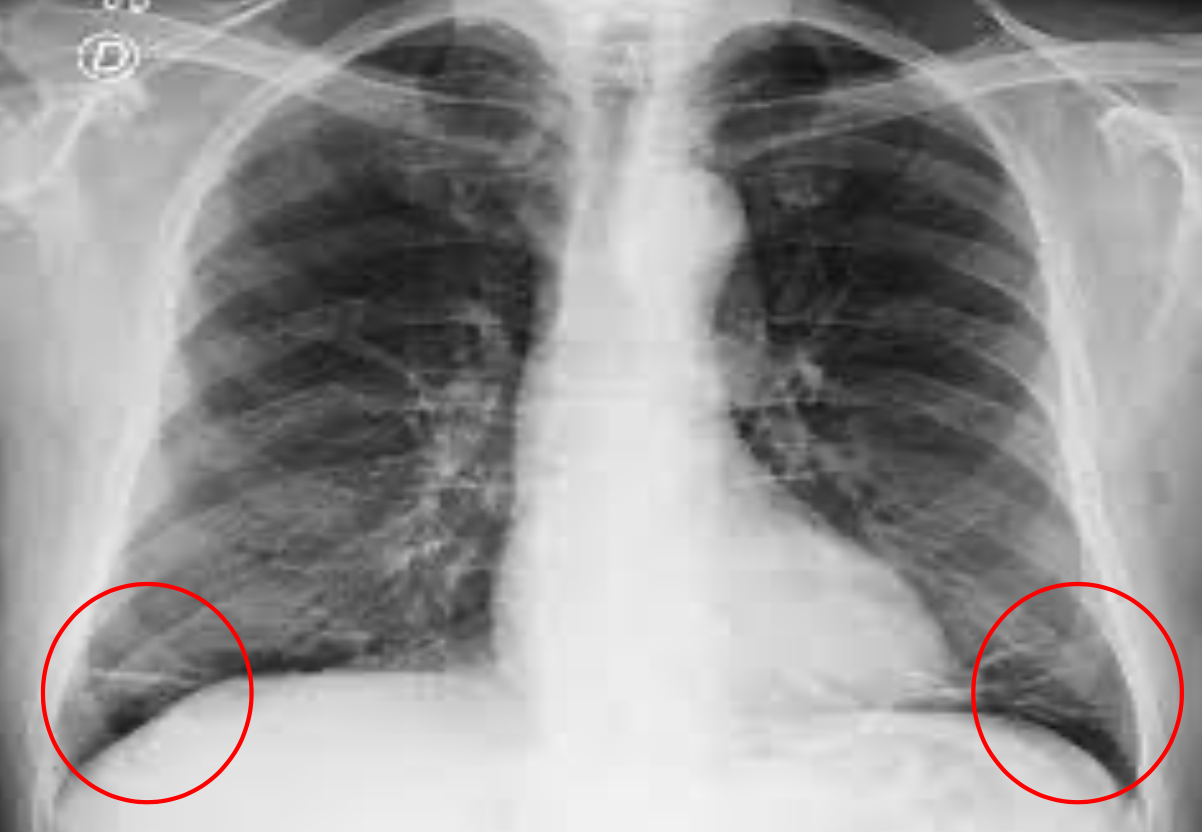

A: edema alveolar B: líneas B de Kerley C: cardiomegalia D: dilatación de vasos en lóbulos superiores E: derrame pleural

Insuficiencia cardiaca